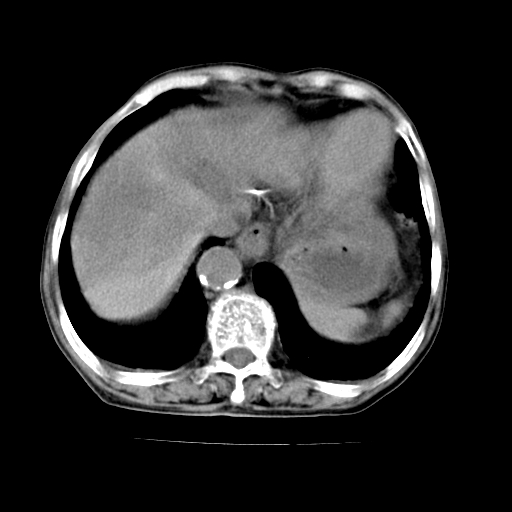

女,68岁,腹胀、恶心两周,先做ct平扫,当时家属不同意强化,6天后家属要求增强扫描。

1、胃窦癌; 2、局灶性脂肪肝。

1、胃窦癌?建议行胃镜!; 2、局灶性脂肪肝。

1.局灶性脂肪肝;2.胃窦癌可能,建议行进一步检查。